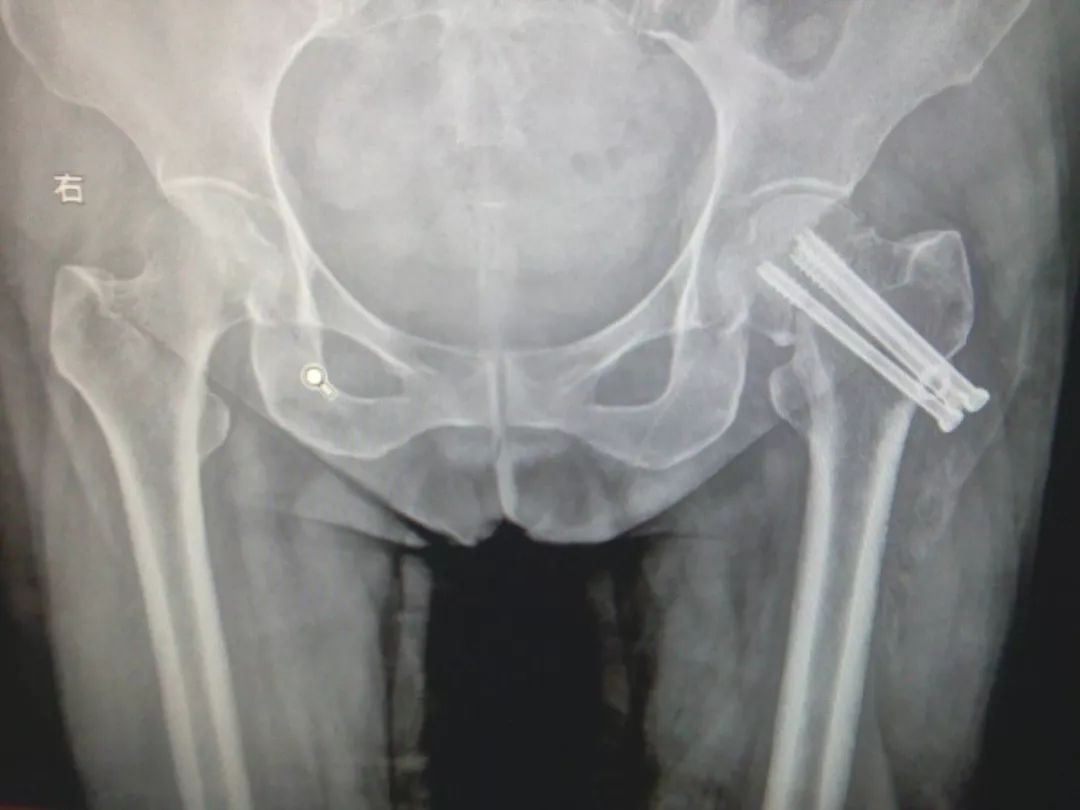

2、外固定:采用经皮穿钢针固定的外固定架方式治疗。

优点:创伤最小,即使身体条件很差的老年人也可以耐受。

缺点:固定力不足,外固定架不方便,妨碍翻身和活动,也不能早期下地。